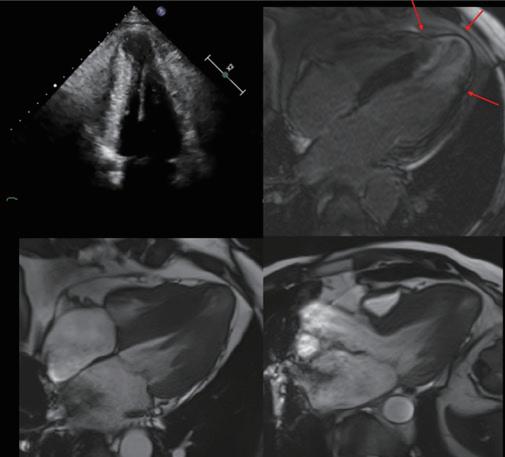

3. 心肌炎引起的纖維化

心肌炎可導致局部纖維化,最常見的發生在側壁及心尖區域。這些患者的心臟磁振造影檢查中,常見心外膜下 (subepicardium) 疤痕,尤其在SARS-CoV-2相關心肌炎患者中更為顯著。急性心肌炎後,部分患者可進展為慢性 炎症性心肌病,且心臟磁振造影檢查中的LGE分佈可作為預後風險的重要指標。 (圖四) 中華民國心律醫學

(圖四)、慢性炎症性心肌病